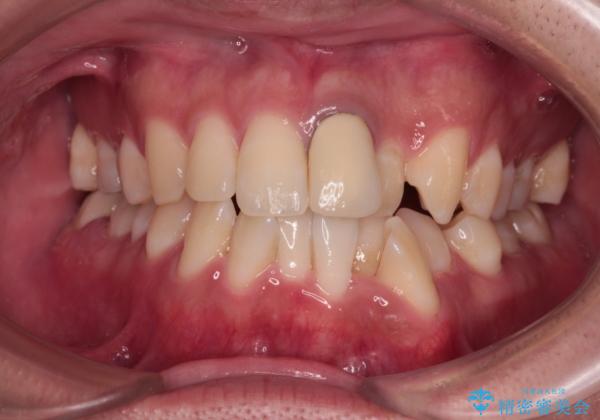

気になる前歯のデコボコと八重歯 ワイヤー矯正ですっきりと

上下ともに歯列幅が狭く、その影響でデコボコになっていたため、ワイヤー装置を用いて歯列を側方に拡大しながら、デコボコを解消していくこととしました。

矯正治療後には気になっていた前歯をセラミッククラウンにし、自然な口元に仕上げることができました。